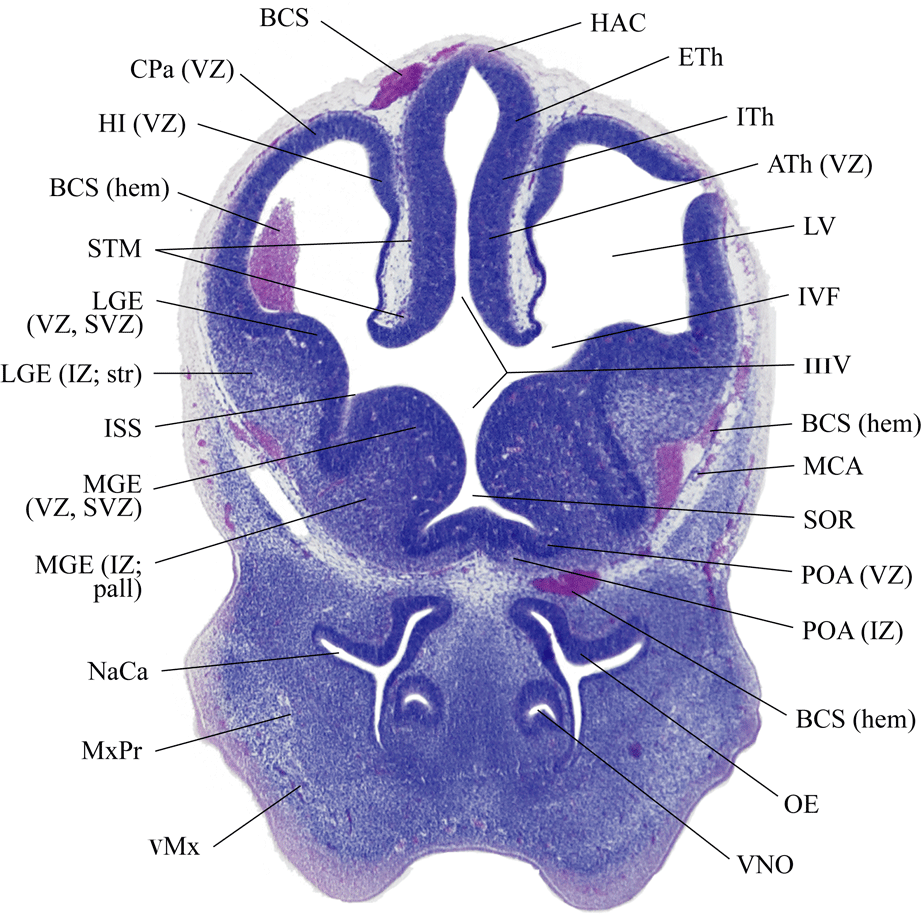

Coronal sections of gestational day (GD) 12 mouse heads, every 5th. section, stained with a hematoxylin and eosin (H & E).

[Download abbreviations file]